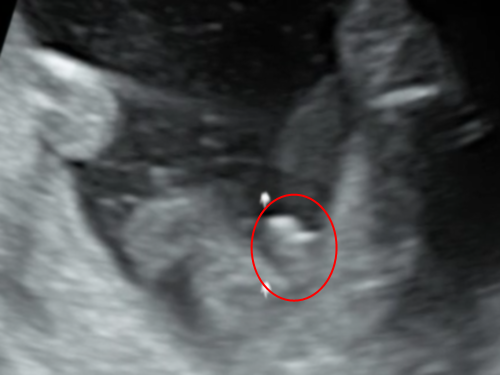

エコー 女の子 木の葉. 妊娠 - エコーでみる赤ちゃんの性別(山が二つで女の子?) 妊娠34週に入りました。 先日までまだ性別が確定していなかったのですが、 エコーの結果、先生に女の子だと言われました。 股の下からの画像では... 女の子の証拠エコー「木の葉形」を 41歳5人目にして 初めて知ったjunなのでした☆ でも思い出してみると 先月に男の子って言われて 「妊娠7ヶ月 エコー 男の子 間違い」 とかいろいろググって見てる時に 「木の葉」ってキーワードは見た気がする!. 妊娠24週ってどんな時期?! エコーで赤ちゃんの性別が確定できました♡女の子の場合でも断定できる!葉っぱマークや子宮が見えるって本当?? そしてツワリも終わって気をつけたいのが体重管理!! 妊娠中の体重増加の目安って?ツワリで減った場合は、どの時点の体重から考えるべき?.

ゴールデンウィーク イラスト-ゴールデンウィーク イ ;. エコーで木の葉型だったら女の子? 妊娠中 コメントの数:4 ハートの数:0 エコーで突起物やピーナッツ型のようなものが見えたら男の子、股の間に木の葉のようなものが見えたら女の子って聞きませんか?. こちらの記事に対するkozokaeruさんのブックマークです → 「“胎児 エコー 女の子 割れ目女の子 エコー 木の葉 写真女の子 エコー 突起物 画像エコー写真 男の子 女の子 違い女の子 エコー 写真 突起物男の子エコー写真股女の子 エコー 写真 葉っぱ妊娠 性別 エコー 見分け方エコー 」.

赤ちゃんがお腹の中にいることが分かると、とても幸せな気持ちになますね。 妊娠が発覚して、まず何が気になるって…赤ちゃんの性別です!! うちのパパは女の子希望でしたので、ずっとエコー写真を見ては 「これは女の.. 女の子エコー写真股 — エコー検査で、赤ちゃんの性別が判明するのはいつごろなのでしょうか。写真の見分け方や男の子、女の子それぞれの見え方の特徴を画像付きで解説します。男の子はピーナツ状の突起物、女の子は木の葉やコーヒー豆が股間に見えますが、ときには判定間違いも起こり .. エコー写真から性別判定お願いします 妊娠28週です 担当の先生には男 こちらの記事に対するkozokaeruさんのコメントです 胎児 エコー 女の子 割れ目女の子 エコー 木の葉 写真女の子 エコー 突起物 画像エコー写真 男の子 女の子 違..

女の子 の場合は、突起物はなく、 太ももの間に 木の葉のようなもの が見えます。 また、子宮と膀胱がふたつの黒い点として エコー写真に写ります。 ※女の子に恵まれれば、いつか写真参考アップしますね٩(•౪• ٩).